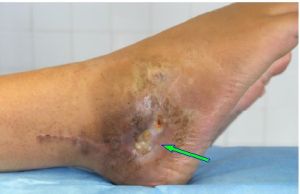

骨髓炎骨髓炎是指化膿性細菌感染骨髓、骨皮質和骨膜而引起的炎症性疾病,多數由血源性引起,也多由外傷或手術感染引起,多由癤癰或其他病灶的化膿菌毒進入血液而達骨組織。四肢骨兩端最易受侵,尤以髖關節為最常見 。臨床上常見有反覆發作,嚴重影響身心健康和勞動能力。急性骨髓炎起病時高熱、局部疼痛,轉為慢性骨髓炎時會有潰破、流膿、有死骨或空洞形成。重症患者常危及生命,有時不得不採取截肢的應急辦法,致患者終生殘疾。

3.癌變

竇道口皮膚由於不斷受刺激,可合併癌變,常見為鱗狀上皮癌。